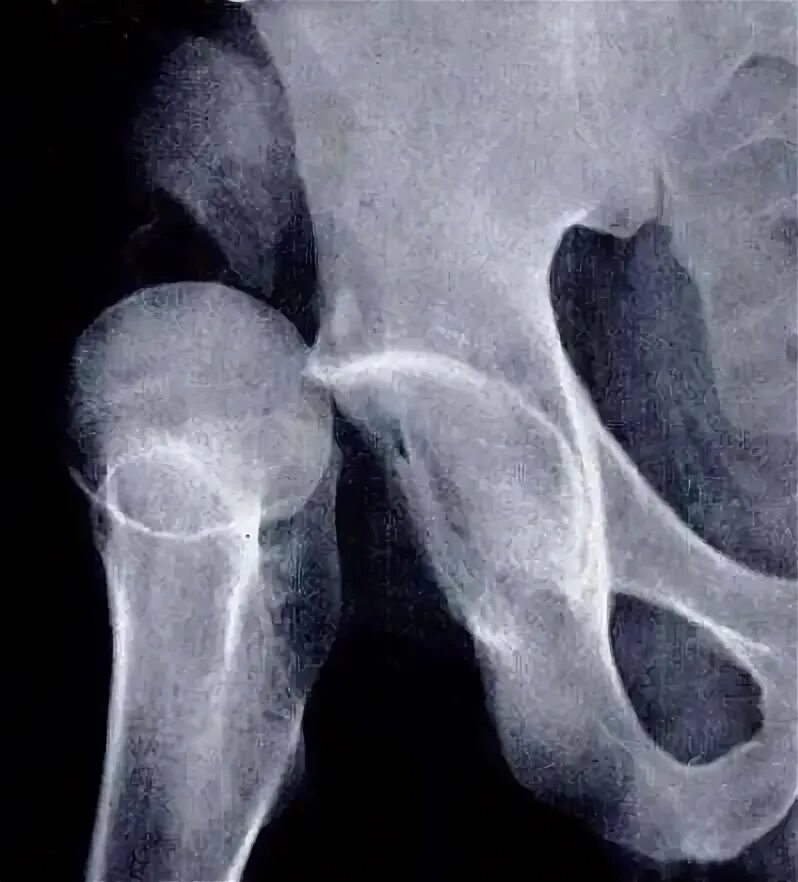

Повреждение связок тазобедренного сустава